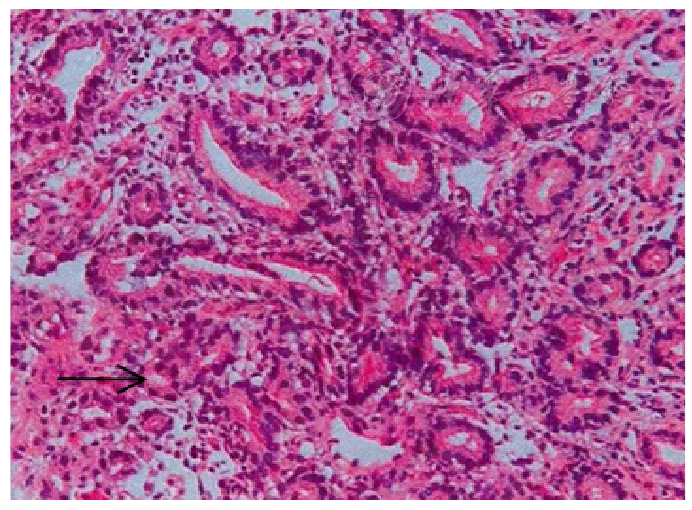

图1 患者典型残胃黏膜肠化生、萎缩和不典型增生(HE染色、×200)

图2 患者典型残胃黏膜高分化腺癌(HE染色、×200)